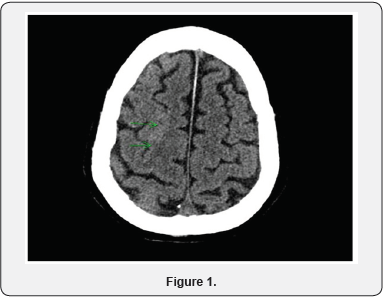

70 years old male who was recently in Philippines and came back 2 days prior to admission, was seen in the emergency department for fever and global headache. He had these symptoms for about 2-3 days. He denied vomiting, diarrhea and any sick contacts. His past medical history was significant for coronary artery disease with remote history of quadruple bypass and also diabetes mellitus type 2. He denied any history of smoking or alcohol abuse. On arrival he was febrile at 100.8 degree Fahrenheit. Physical exam was notable for mild neck tenderness and rigidity. He was oriented to person and place but not time. Computed tomography (CT) of brain showed no soft tissue mass, acute infarct or hemorrhage but it was noted that patient has asymmetry of right superior frontal sulcus that could be secondary to gyral swelling (Figure1). Magnetic resonance imaging could not be done since the patient had sternal wires. Lumbar puncture was done and cultures of cerebrospinal fluid (CSF) later came back positive for HSV1.